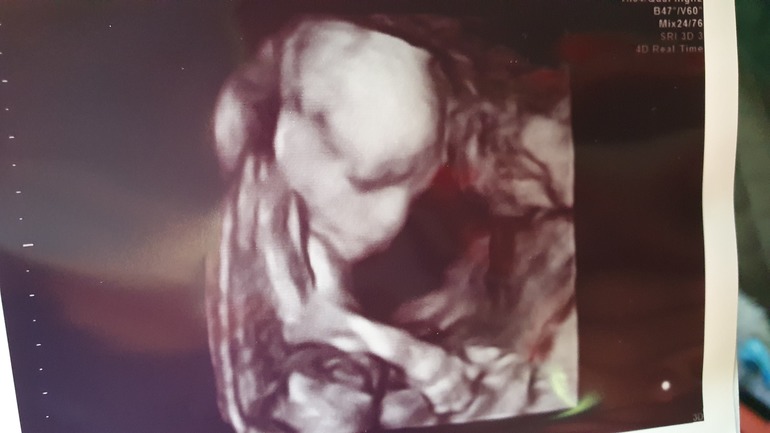

Заводная колбасень =)

26ая неделя. Наконец-то наступил тот срок, когда я ну очень отчетливо чувствую каждый пинок. (В связи со спинальной травмой, я чувствую живот ни как все). И теперь, я 24 на 7 ощущаю темперамент нашей младшенькой. Лежать нам не по приколу, долбим в матрас так, ч...